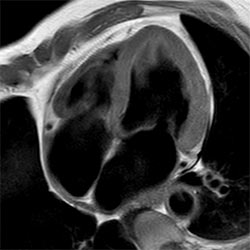

In a society where reimbursements are declining and chronic conditions lead to increased MR procedures and longer waiting times, there is ever increasing pressure on the radiology department. Today, further attempts to accelerate, compromise image quality or are limited to a narrow range of scans. Therefore, to meet the increased demand for productivity, a technology break-through in acceleration is still required. Leveraging our long standing leadership position in speed (i.e. SENSE), Philips brings compressed SENSE, a breakthrough in productivity.

Learn more about the main principles of Compressed SENSE and how it introduces a paradigm shift in productivity, how Compressed SENSE was designed around image quality, and how it advances productivity for clinical MR imaging.